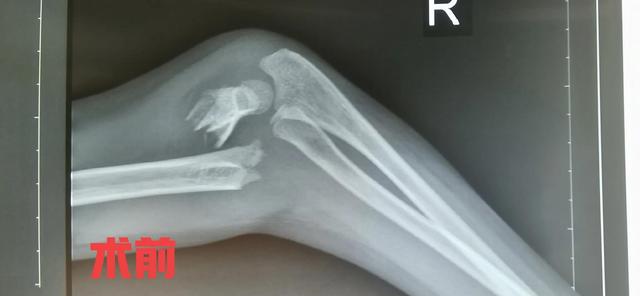

肱骨髁上骨折一般是指肱骨内、外髁上2cm范围内的骨折,在小儿骨折中非常常见的一种骨折,多见于3到12岁的小孩,在小儿肘关节骨折中占比达到80%以上。该骨折可合并血管,神经的损伤,处理不当可引起缺血性肌挛缩,骨化肌炎,肘关节内外翻畸形等。对于非移位骨折或者不完全性骨折单纯石膏托外固定就可以。对于有明显移位的骨折,以前通常都是通过闭合手法复位加石膏托外固定,由于骨折端难以复位,或者骨折端的不稳定性,患肢消肿,石膏托松紧度改变,容易导致骨折复位丢失,甚至骨折复位失效,骨折再次移位,再次复位效果欠佳,反复调节增加小儿痛苦等。目前逐渐倾向于手术治疗,主要采用手法闭合复位克氏针内固定,辅助石膏托外固定,是一种零切开的微创手术,患儿家长容易接受的一种术式。没有特殊情况,基本上手术当天或者术后第一天就可以出院。

病例 女性,7岁,跌伤,右肱骨髁上骨折